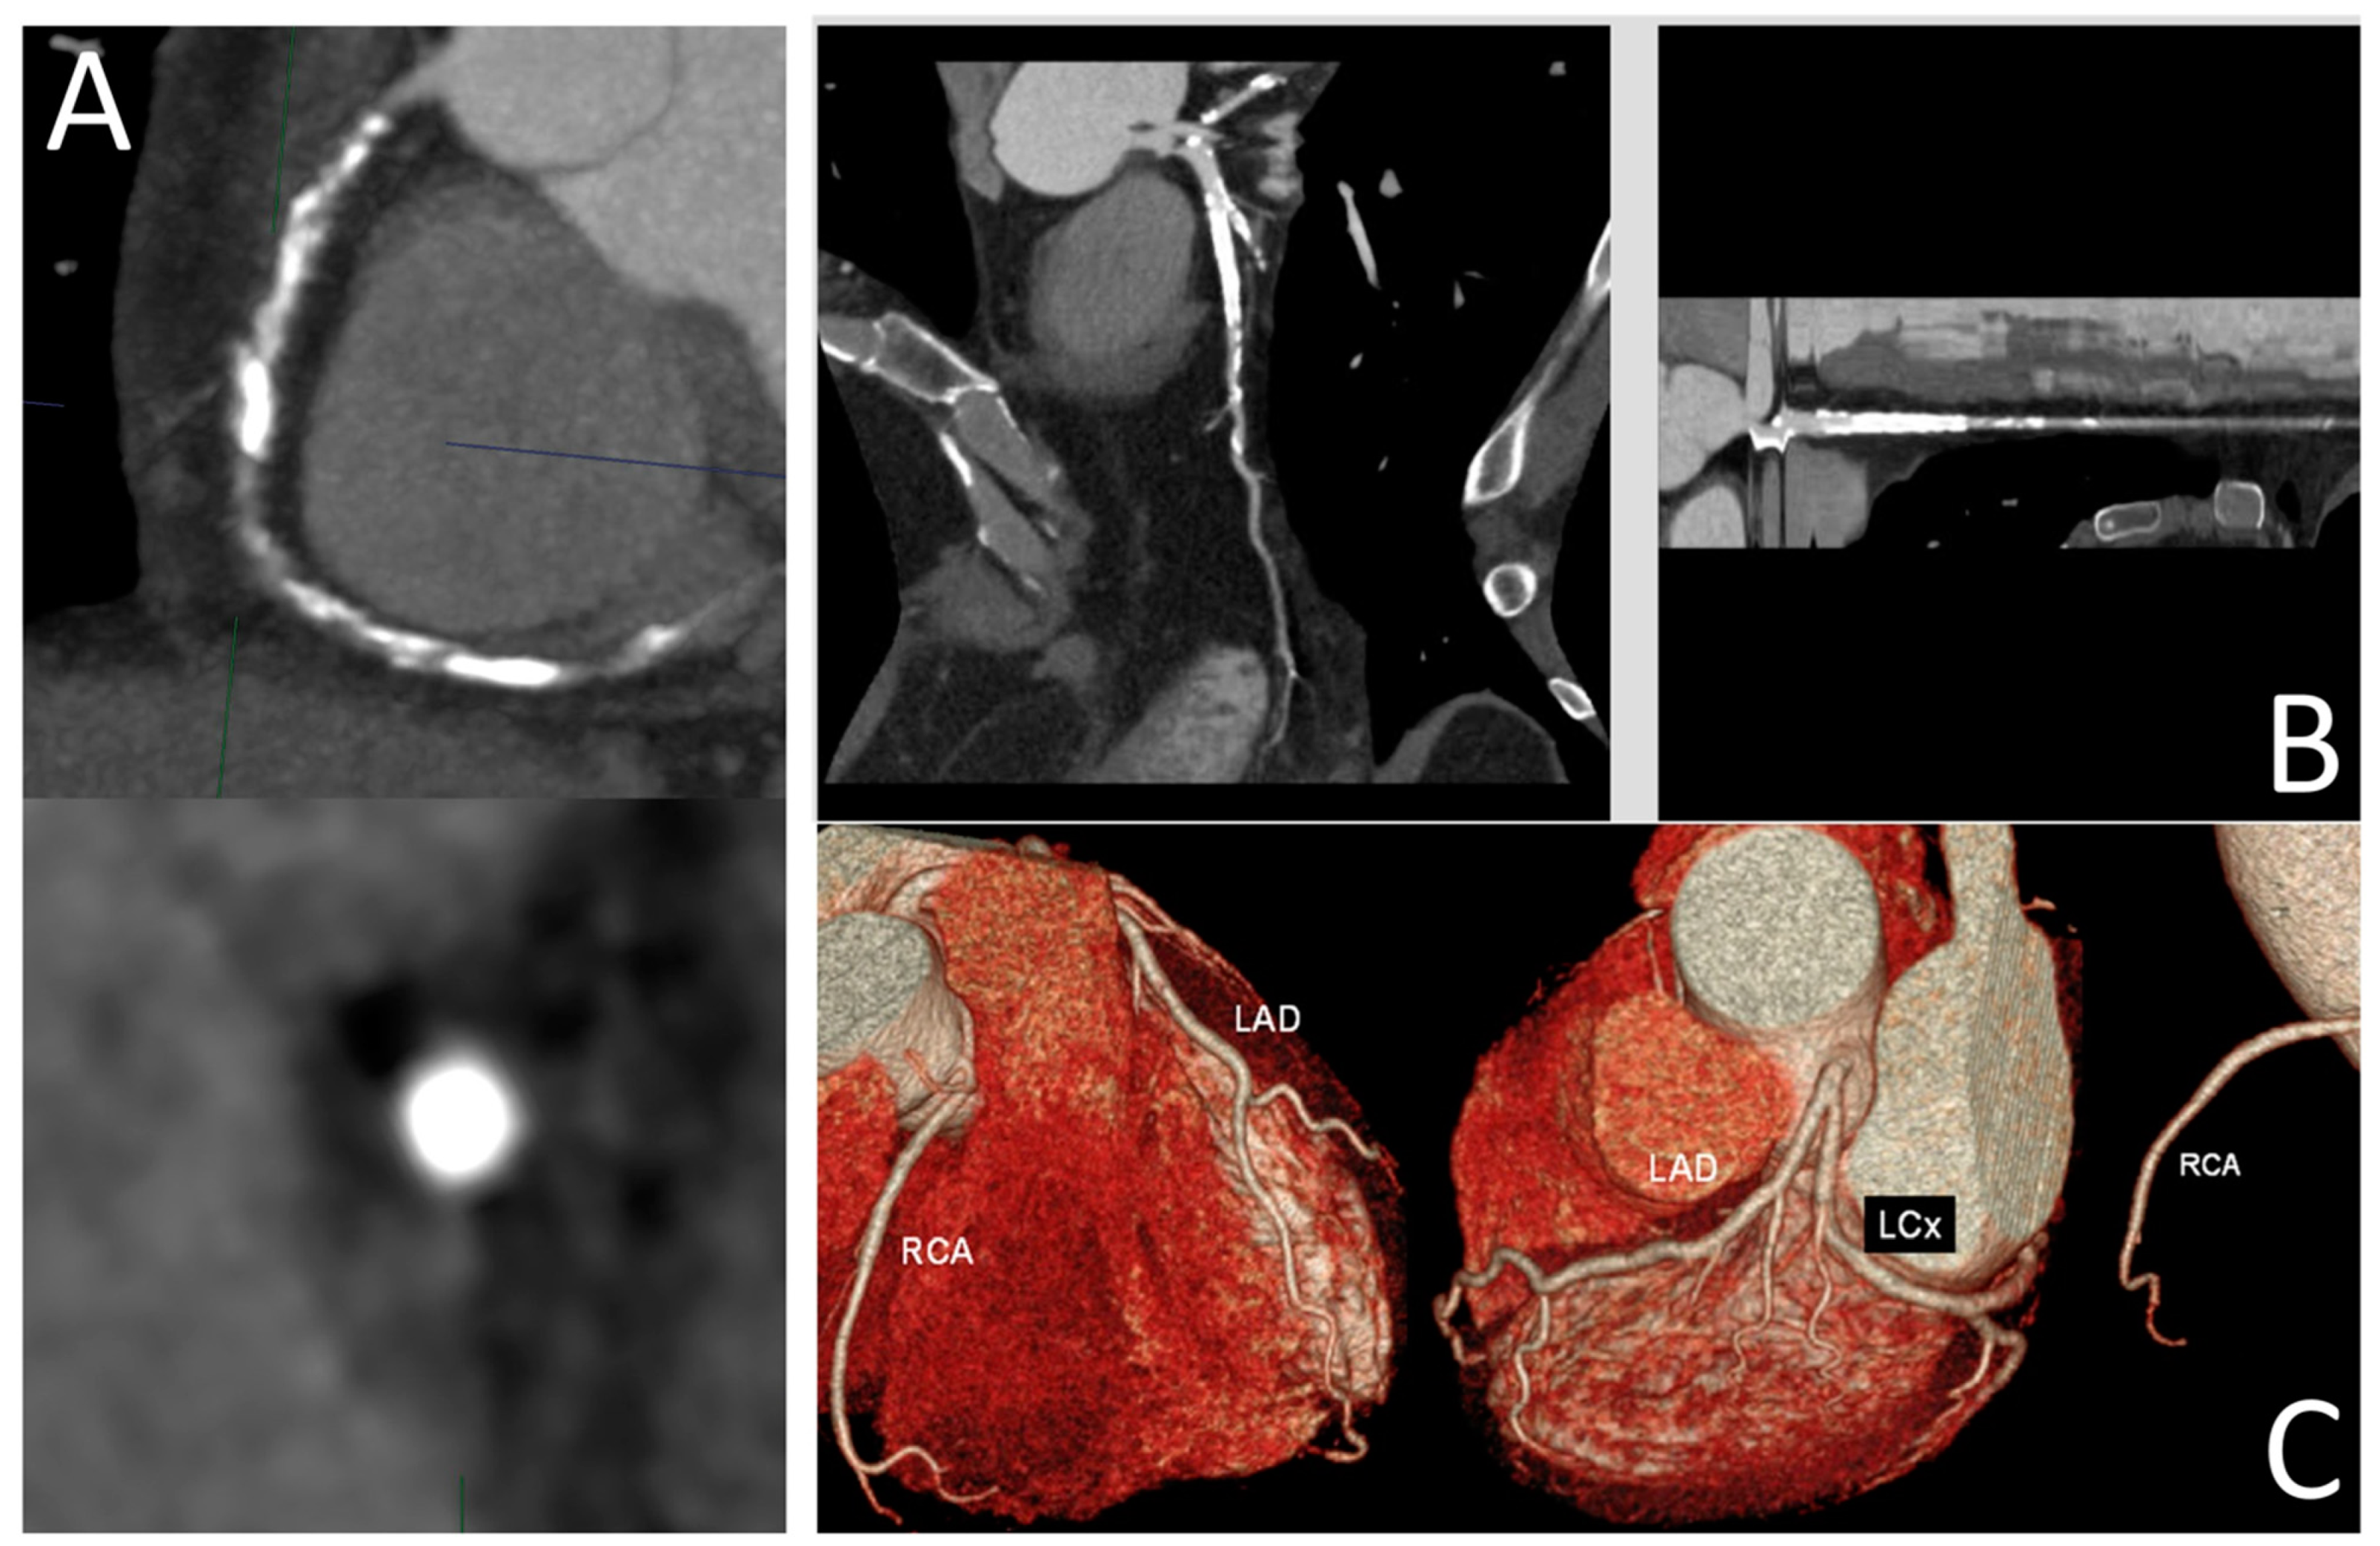

3. Coronary Computed Tomography Angiography (CCTA)

- Panuccio, G.; Werner, G.S.; De Rosa, S.; Torella, D.; Leistner, D.M.; Siegrist, P.T.; Haghikia, A.; Skurk, C.; Mashayekhi, K.; Landmesser, U.; et al. Full-Moon Coronary Calcification as Detected with Computed Tomography Angiography in Chronic Total Occlusion Percutaneous Coronary Intervention. Am. J. Cardiol. 2024, 222, 149–156. [Google Scholar] [CrossRef] [PubMed]

- Panuccio, G.; Skurk, C.; Landmesser, U.; Abdelwahed, Y.S. Double “Full Moon” CTO Plaque Detected by Computed Tomography Could Predict High-Grade Debulking Techniques: A Case-Report. Clin. Case Rep. 2023, 11, e7325. [Google Scholar] [CrossRef] [PubMed]

| CCTA (Coronary Computed Tomography Angiography) | X-rays | -Non-invasive modality -Slab maximum intensity projection (MIP) allows high-quality images. -Curved and stretched multi-planar (MPR) reconstructions allow easy measurement of occlusion length. -Volume rendering (VR) creates a three-dimensional view of the vessel. -Identification of calcium patterns around the CTO-lesion. -Simulation of angiographic views, friendly to interventional cardiologists. -CCTA based scores (KCCT and CT-rector) predict success rates. | -Lacking real-time imaging during PCI -Contrast and radiation exposure -Blooming effect due to heavy calcification may reduce diagnostic accuracy -Training needed to use CCTA programs -High costs |